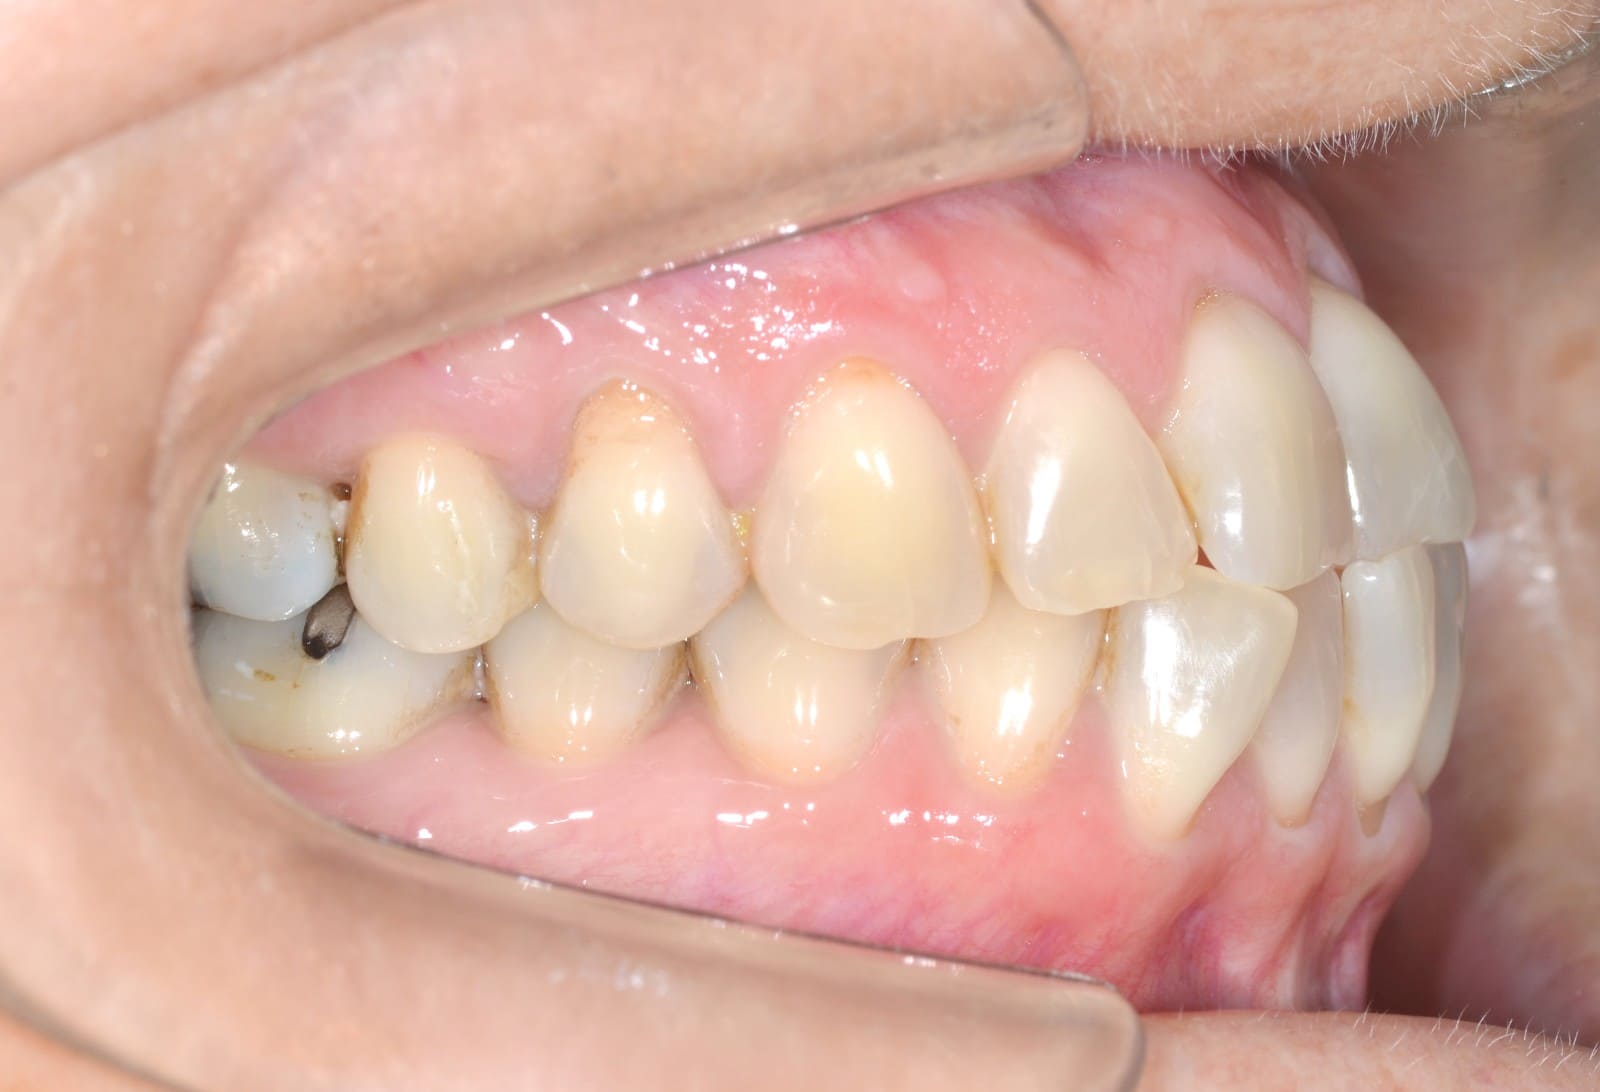

Initial

Final

Invisalign Comprehensive Conditions – Anterior crossbite – Class III – Crowding – Mandibular midline deviation – Rotations

Clinical Indications

- Anterior crossbite

- Class III

- Crowding

- Mandibular midline deviation

- Rotations